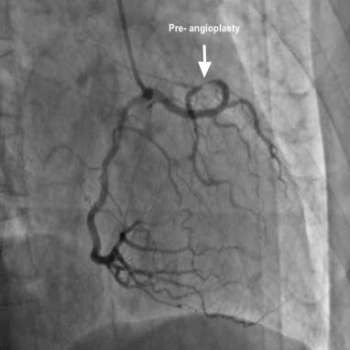

He came to see me with the angio CD and symptoms in May 2018 for the first time. I reviewed the angiogram and mentioned that I am able to do angioplasty for him, even though it is complex- but with special techniques. His creatinine was also noted to be high (2 mg/dl), therefore the contrast load should also be minimised. He agreed and got admitted on 4th June 2018. I performed his angioplasty of his anomalous Cx artery arising from single coronary ositum via radial approach on 5th June 2018.  I used a special mother-and- child catheter to reach the lesion and to reduce the amount of dye usage- managed to use only 50 ml of contrast. The procedure went successfully with deployment of 1 stent  and good flow. He was discharged on 7th June 2018 and his creatinine on discharge date was 1.58 mg/dl.

This is a rare case of stenosis in anomalous circumflex artery arising from single coronary ostium. The risk of this  procedure is higher than LMCA angioplasty as the patient’s heart  is getting blood supply from only one limb- which divides into two. Any damage to the main limb will cause sudden cardiac arrest, therefore the procedure should be done with utmost care to avoid complication.